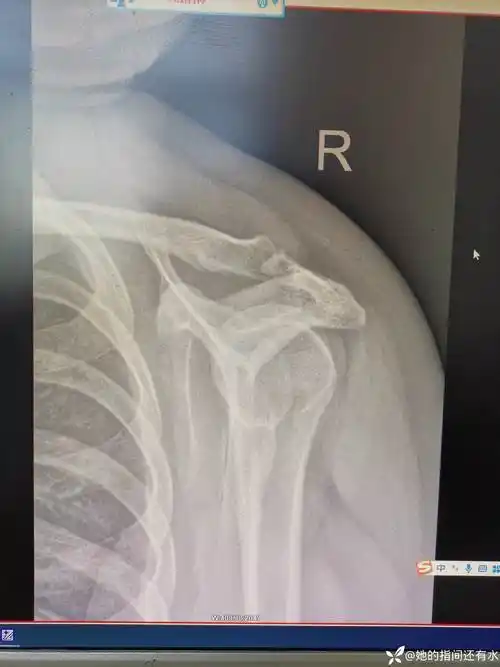

请问右肩锁关节半脱位能有多小几率能评上评残?

肩关节半脱位

患侧上肢向下脱垂,使得韧带松弛上部从关节处下滑,出现肩关节半脱位.